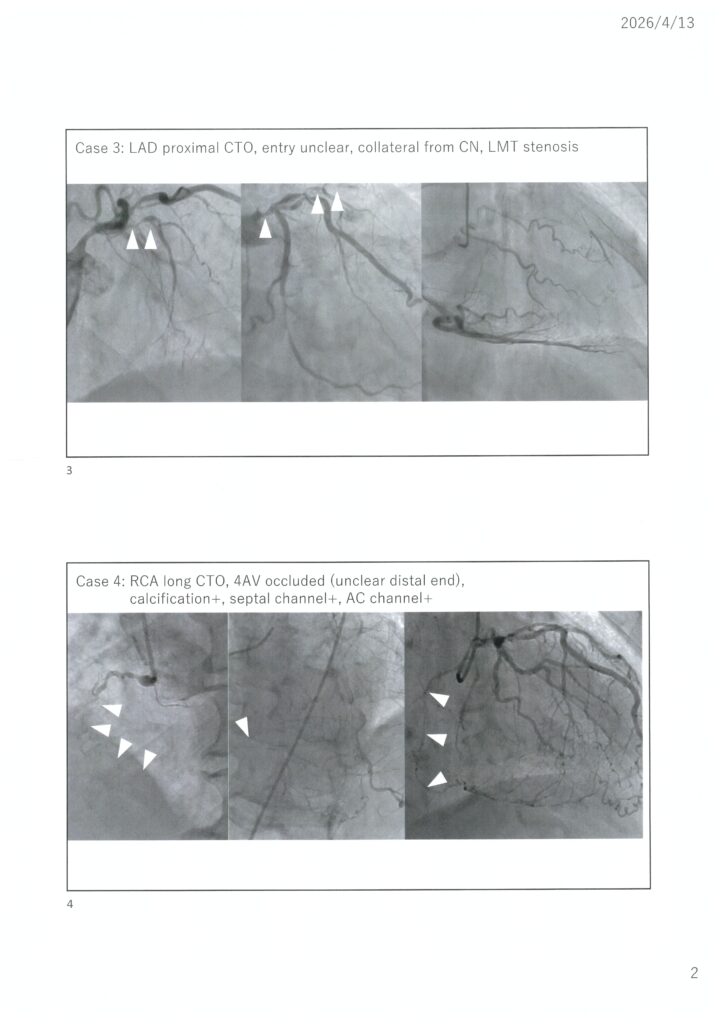

忖度のない我々のCTO治療から何かを学び取っていただければと思いますので、今年も奮ってご参加ください。Case1は伊藤、Case2は保坂Drで午前に治療予定です。Case3は小林、Case4は伊藤、Case5は堤、Case6は小林が午後治療予定です。可能な限り治療の全てをご覧いただけるようスイッチングなども考慮しつつ開催できればと思います。